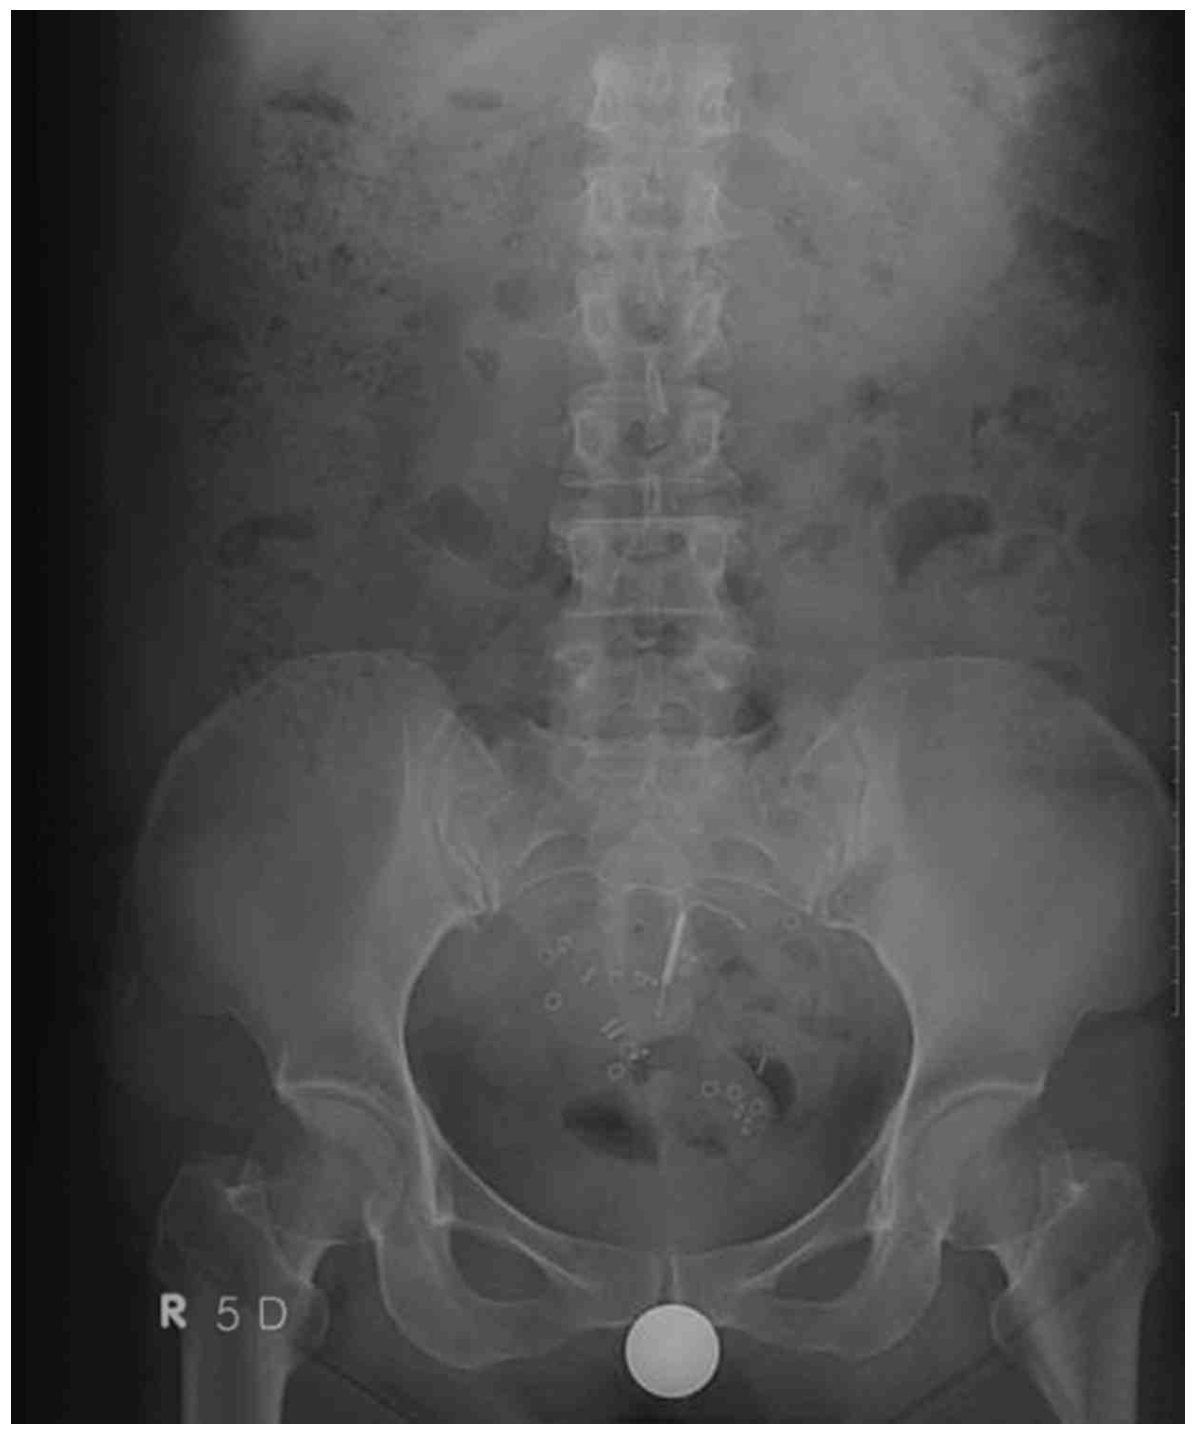

대장통과시간 측정 검사: radiopaque한 표지자들이 직장/항문에 집중적으로 존재

• 대장통과시간 검사 결과 radiopaque한 표지자들이 직장/항문 주위에서 집중적으로 관찰되는데, 이는 골반저 기능장애를 시사하는 소견이다.